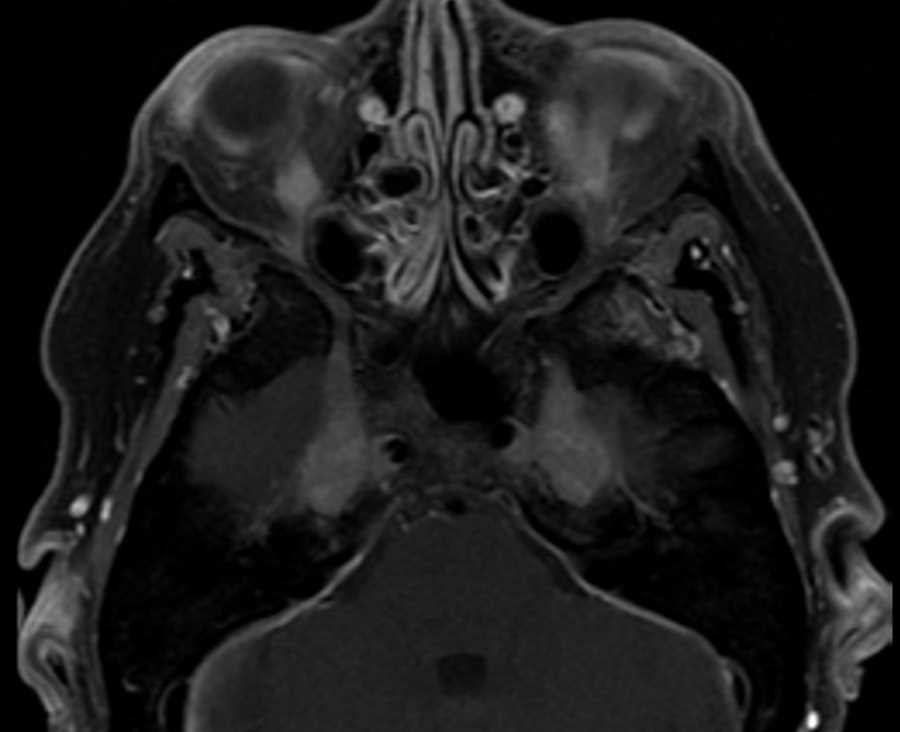

Rosai-Dorfman

There is thick pachymeningeal enhancement along the falx and tentorial leaflets as well as along the medial aspects of the middle cranial fossae extending into Meckel’s caves and foramina ovale along the course of the branches of the V2 and V3 segments of the trigeminal nerves. Enhancement extends into the masticator spaces and pterygopalatine fossae. Findings can be seen in granulomatous diseases, lyme disease, neurofibromatosis, lymphoma, or histiocytosis. This case turned out to be CNS Rosai-Dorfman, a benign disease characterized by massive lymphadenopathy and variable extranodal involvement of the dura, sinuses, skin, orbits, bone, and salivary glands. CNS manifestations are usually that of enhancing dural based masses as seen here. The diagnosis is made by biopsy and patients are usually monitored and treated symptomatically with tumor debulking as needed.